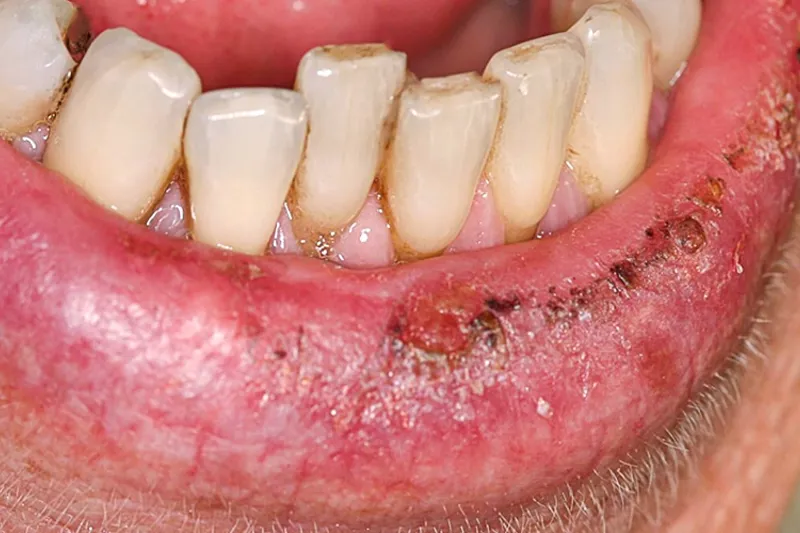

Aktinisk keratose viser sig som:

· Skorpe- eller skældannelse på prolabiet, ofte samtidig med grålig/hvidlig/gullig forandring og uskarp afgrænsning af prolabiet i forhold til omgivende hud

· Tørre og skællende læber

· Fissurer og erosioner på læberne

· Vedvarende sår på prolabiet

· Hævelser af læberne

Aktinisk keratose ses oftest på underlæben og kan optræde som en lokaliseret forandring, men typisk vil en større del af læben være involveret. Tilstanden kan være asymptomatisk eller forbundet med sviende, brændende fornemmelse i læben.